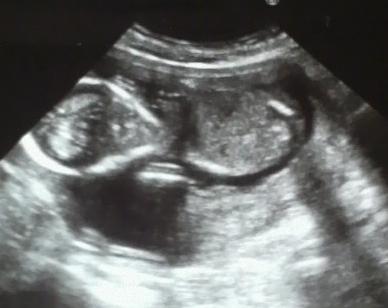

5ヶ月半ば、17週目のジロー君でございます。

ジャジャン☆

ジローくん♪

左が頭で右が足。

ところで、これ、脳みそ見えてるよ・・・ね?(´ω`;)

顔らしきものも、見えるよ、ね??

今の所はエイリアンジローです(まて

残念ながら今回は性別わかりませんでした(´・ω・`)

心臓がバックバクしてるのがはっきり見えて、感動した。

でもエコー写真の方は私もよくわかりませんww

どうやら今のジローは253gであるらしい、という事くらいしか解読できませんwwwww